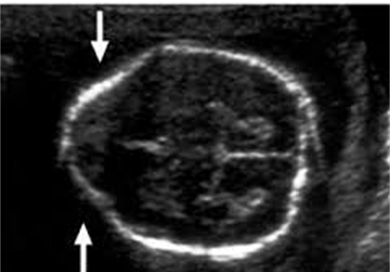

What are these images showing?

Facial Evaluation